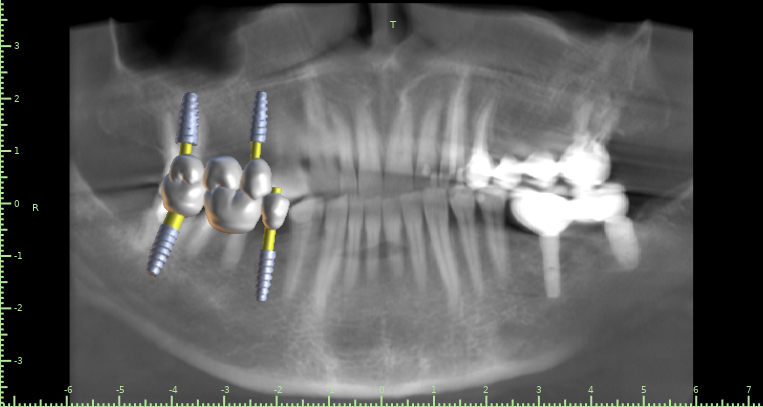

Женька Опубликовано 10 декабря, 2021 Автор Поделиться Опубликовано 10 декабря, 2021 @kamranchick чисто винтами? или нужно ортодонта подключить? Планируется вот так Ссылка на комментарий

АнтонТЛТ Опубликовано 10 декабря, 2021 Поделиться Опубликовано 10 декабря, 2021 А ортопед не хочет немного шлифануть этот зуб? Винты ставить из-за 1.5 мм, как-то жёстко) Планирование в каком софте? 2 Ссылка на комментарий

Женька Опубликовано 11 декабря, 2021 Автор Поделиться Опубликовано 11 декабря, 2021 @АнтонТЛТ blue sky plan Антон, я передам эти мысли ортопеду А подождите, я же скорее всего сам и буду это протезировать . И пожалуйста, объясните мне когда можно шлифовать, а когда это овер трит. Я же правильно понимаю, что немного шлифануть, это оставить его без покрытия коронкой? Ссылка на комментарий

АнтонТЛТ Опубликовано 11 декабря, 2021 Поделиться Опубликовано 11 декабря, 2021 В Блю скае есть ортодонтический модуль, можно элайнеры сделать и задвинуть немного этот зуб) Шлифовать в пределах эмали. Попросите техника отмоделировать зубы, будет понимание на сколько можно сошлифовать. Ссылка на комментарий